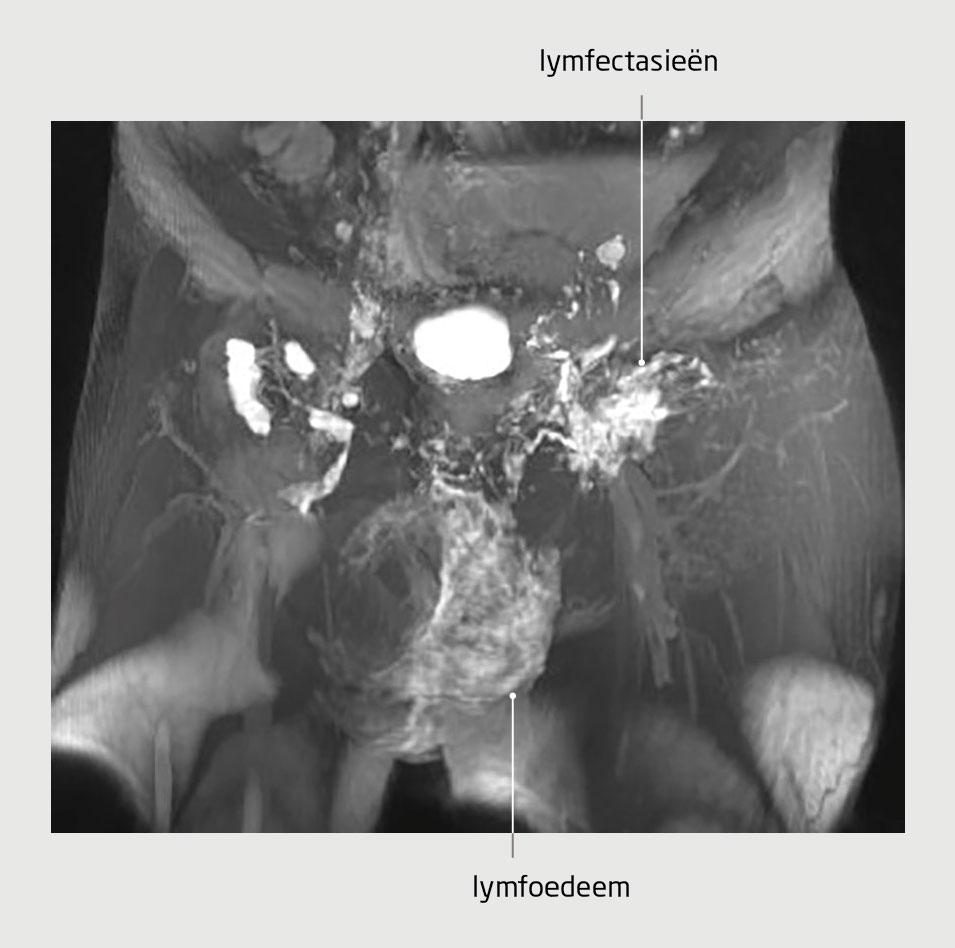

Ruim 30 jaar na de eerste presentatie van deze patiënt liet hij zich naar ons centrum verwijzen voor secundaire beoordeling. Wij zagen een vergroot scrotum met hierop blaasjes waaruit melkachtig vocht lekte. Daarop stelden wij de diagnose ‘chyloscrotum, waarschijnlijk secundair aan de lymfklierdissectie en het preëxistent afwijkende lymfatische stelsel’. Er werd een intranodale dynamische MR-lymfangiografie verricht, waarop een retrograde flow van lymfe vanuit de lies via lymfectasieën naar het scrotum werd aangetoond (figuur 4). De interventieradioloog emboliseerde deze lymfectasieën met lipiodol-histoacryl. Hierna nam het chyloscrotum sterk af, verdween de lekkage en trad goede klinische verbetering in.